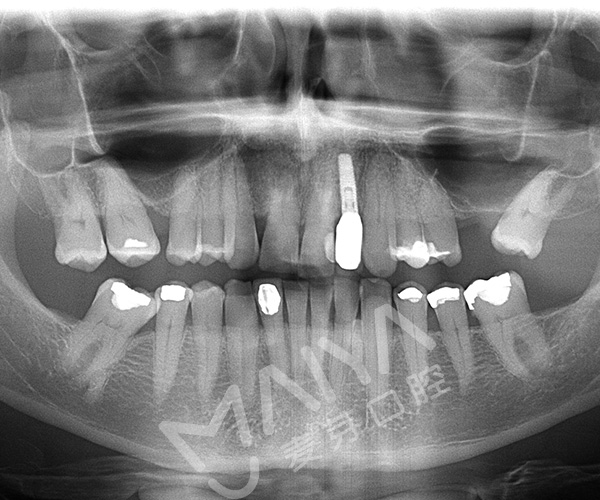

种完牙的口腔全景片

郑院长经过权威分析制定再次种植牙手术的种植方案,首先为Jack拔出患牙做了GPR植骨和保持位点手术,等四个月后缺牙部位形成很好的新骨,再次种牙。

四个月后的Jack再次来院,经过麦芽口腔团队的努力,成功为Jack种上了牙齿,恢复了原有牙列的完美形态,手术的成功使这位德国男子的笑容更加灿烂。